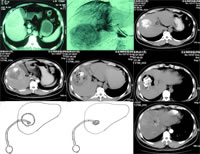

图1 CT显示右肝巨大肝癌

图2 血管造影,显示右肝癌体积大,且血供丰富

图3 TACE后复查CT,显示癌灶内填充的碘剂将肝癌的轮廓显示得较为清晰

图4 第一次射频消融治疗后,见癌灶己得到大部分消融,但周边仍有可疑残留组织

图5 第二次射频消融治疗后8天,复查CT,见癌灶坏死较为完全

图6 第二次射频消融治疗后22天,复查CT,见射频消融区呈缩小和液化趋势

图7 液化灶内置管引流

图8 液化灶明显缩小

图9 射频消融区液化灶穿刺置管引流术后2个月复查CT,见液化腔消失,未见癌组织残留, 百拇医药

患者,男性,49岁,河北籍,发现慢性乙型肝炎5年。2007年1月,因右上腹胀痛不适1周、CT提示“右肝巨块型癌,8.5 cm×7.5 cm×6.6 cm”(图1)来我院就诊。考虑到右肝癌体积大,且有肝硬化门静脉高压症背景,若采取手术切除,需要切除近乎50%的肝脏,术后发生感染、出血、肝功能不全等严重并发症的可能性大,风险高,故制定了RFA联合经导管肝动脉化疗栓塞(TACE)的局部治疗方案。具体如下述。

第一步:先行TACE

2007年3月27日,行血管造影和介入栓塞治疗。血管造影显示“右肝癌体积大,且血供丰富(图2)”。TACE达到了三方面的目的:①进一步明确HCC病灶的范围,排除了超声、CT遗漏病灶的可能性;②减少了癌灶内的血液供应,以期提高RFA效率;③对HCC行局部化疗,并以期提高HCC对RFA治疗的敏感性。2007年4月17日复查CT,显示癌灶内碘剂栓塞效果良好(图3)。

第二步:CT定位下RFA

2007年4月23日,在CT定位下行经皮肤RFA。2007年4月28日,增强CT显示“癌灶己得到大部分消融,但周边仍有可疑残留组织(图4)”。为了更彻底地清除癌灶,于2007年4月30日再次在CT定位下行经皮RFA。

第三步:随访观察

大范围的射频消融,容易产生局部组织坏死、液化,进而可继发感染,需随访观察。第二次RFA后8天,复查CT,见癌灶坏死较为完全(图5)。继之,患者每日下午出现发热,体温通常波动于38℃~39℃,不伴有寒战。再次复查CT,见射频消融区有一定程度的缩小,内有气体积聚,提示有感染(图6)。

第四步:射频消融液化灶穿刺置管引流术

2007年6月1日,在超声定位下行射频消融液化灶穿刺置管引流术,抽出黏稠性液体240 ml,置管后每日冲洗(图7),后逐渐缩小(图8)。2个月后,复查CT,见液化腔消失,拔出引流管后,再行增强CT,见病灶区只留下一炎性小灶,未见癌组织残留(图9)。